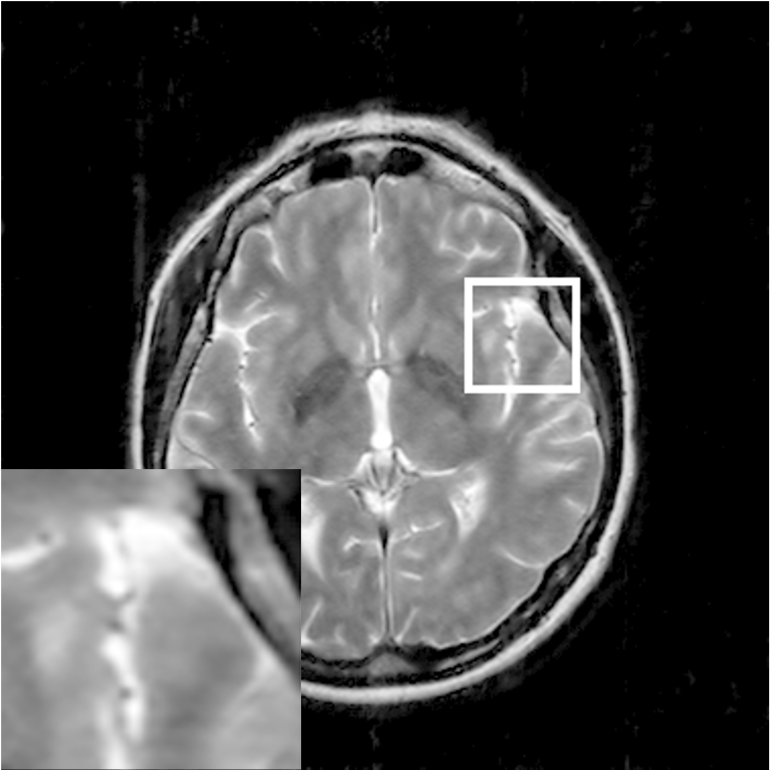

Where x is denoted as the MRI to be reconstructed, y are the k-space data, and Fusubscript𝐹𝑢{F_{u}} represents the under-sampled Fourier encoding matrix. The first term Fuxy22superscriptsubscriptnormsubscript𝐹𝑢xy22{\|{F_{u}}\emph{x}-\emph{y}\|}_{2}^{2} indicates data fidelity that can ensure the consistence between the Fourier coefficients of the reconstructed image and measured data. The second term Risubscript𝑅𝑖{R_{i}} is an analytical, sparsifying transform term, and αisubscript𝛼𝑖{\alpha_{i}} is a factor for balancing data fidelity and transform terms. MR images can be generated by inverse Fourier transform of the sampled k-space data, which are the Fourier coefficient of an object. However, aliasing artifacts (noise-like) are produced by the incoherence of under-sampled k-space in transform domain, as shown in Fig. 1.

Figure 1: The zero-filled reconstruction. (a) is a full-sampled MRI, (b) is a 20% radial sampling mask, (c) is the zero-filled reconstruction under (b), and (d) is the reconstruction using our method. Note that aliasing artifacts are clearly seen in the zero-filled reconstruction (c), which impair diagnostic information. However, our algorithm can remove these unpleasant artifacts (d).